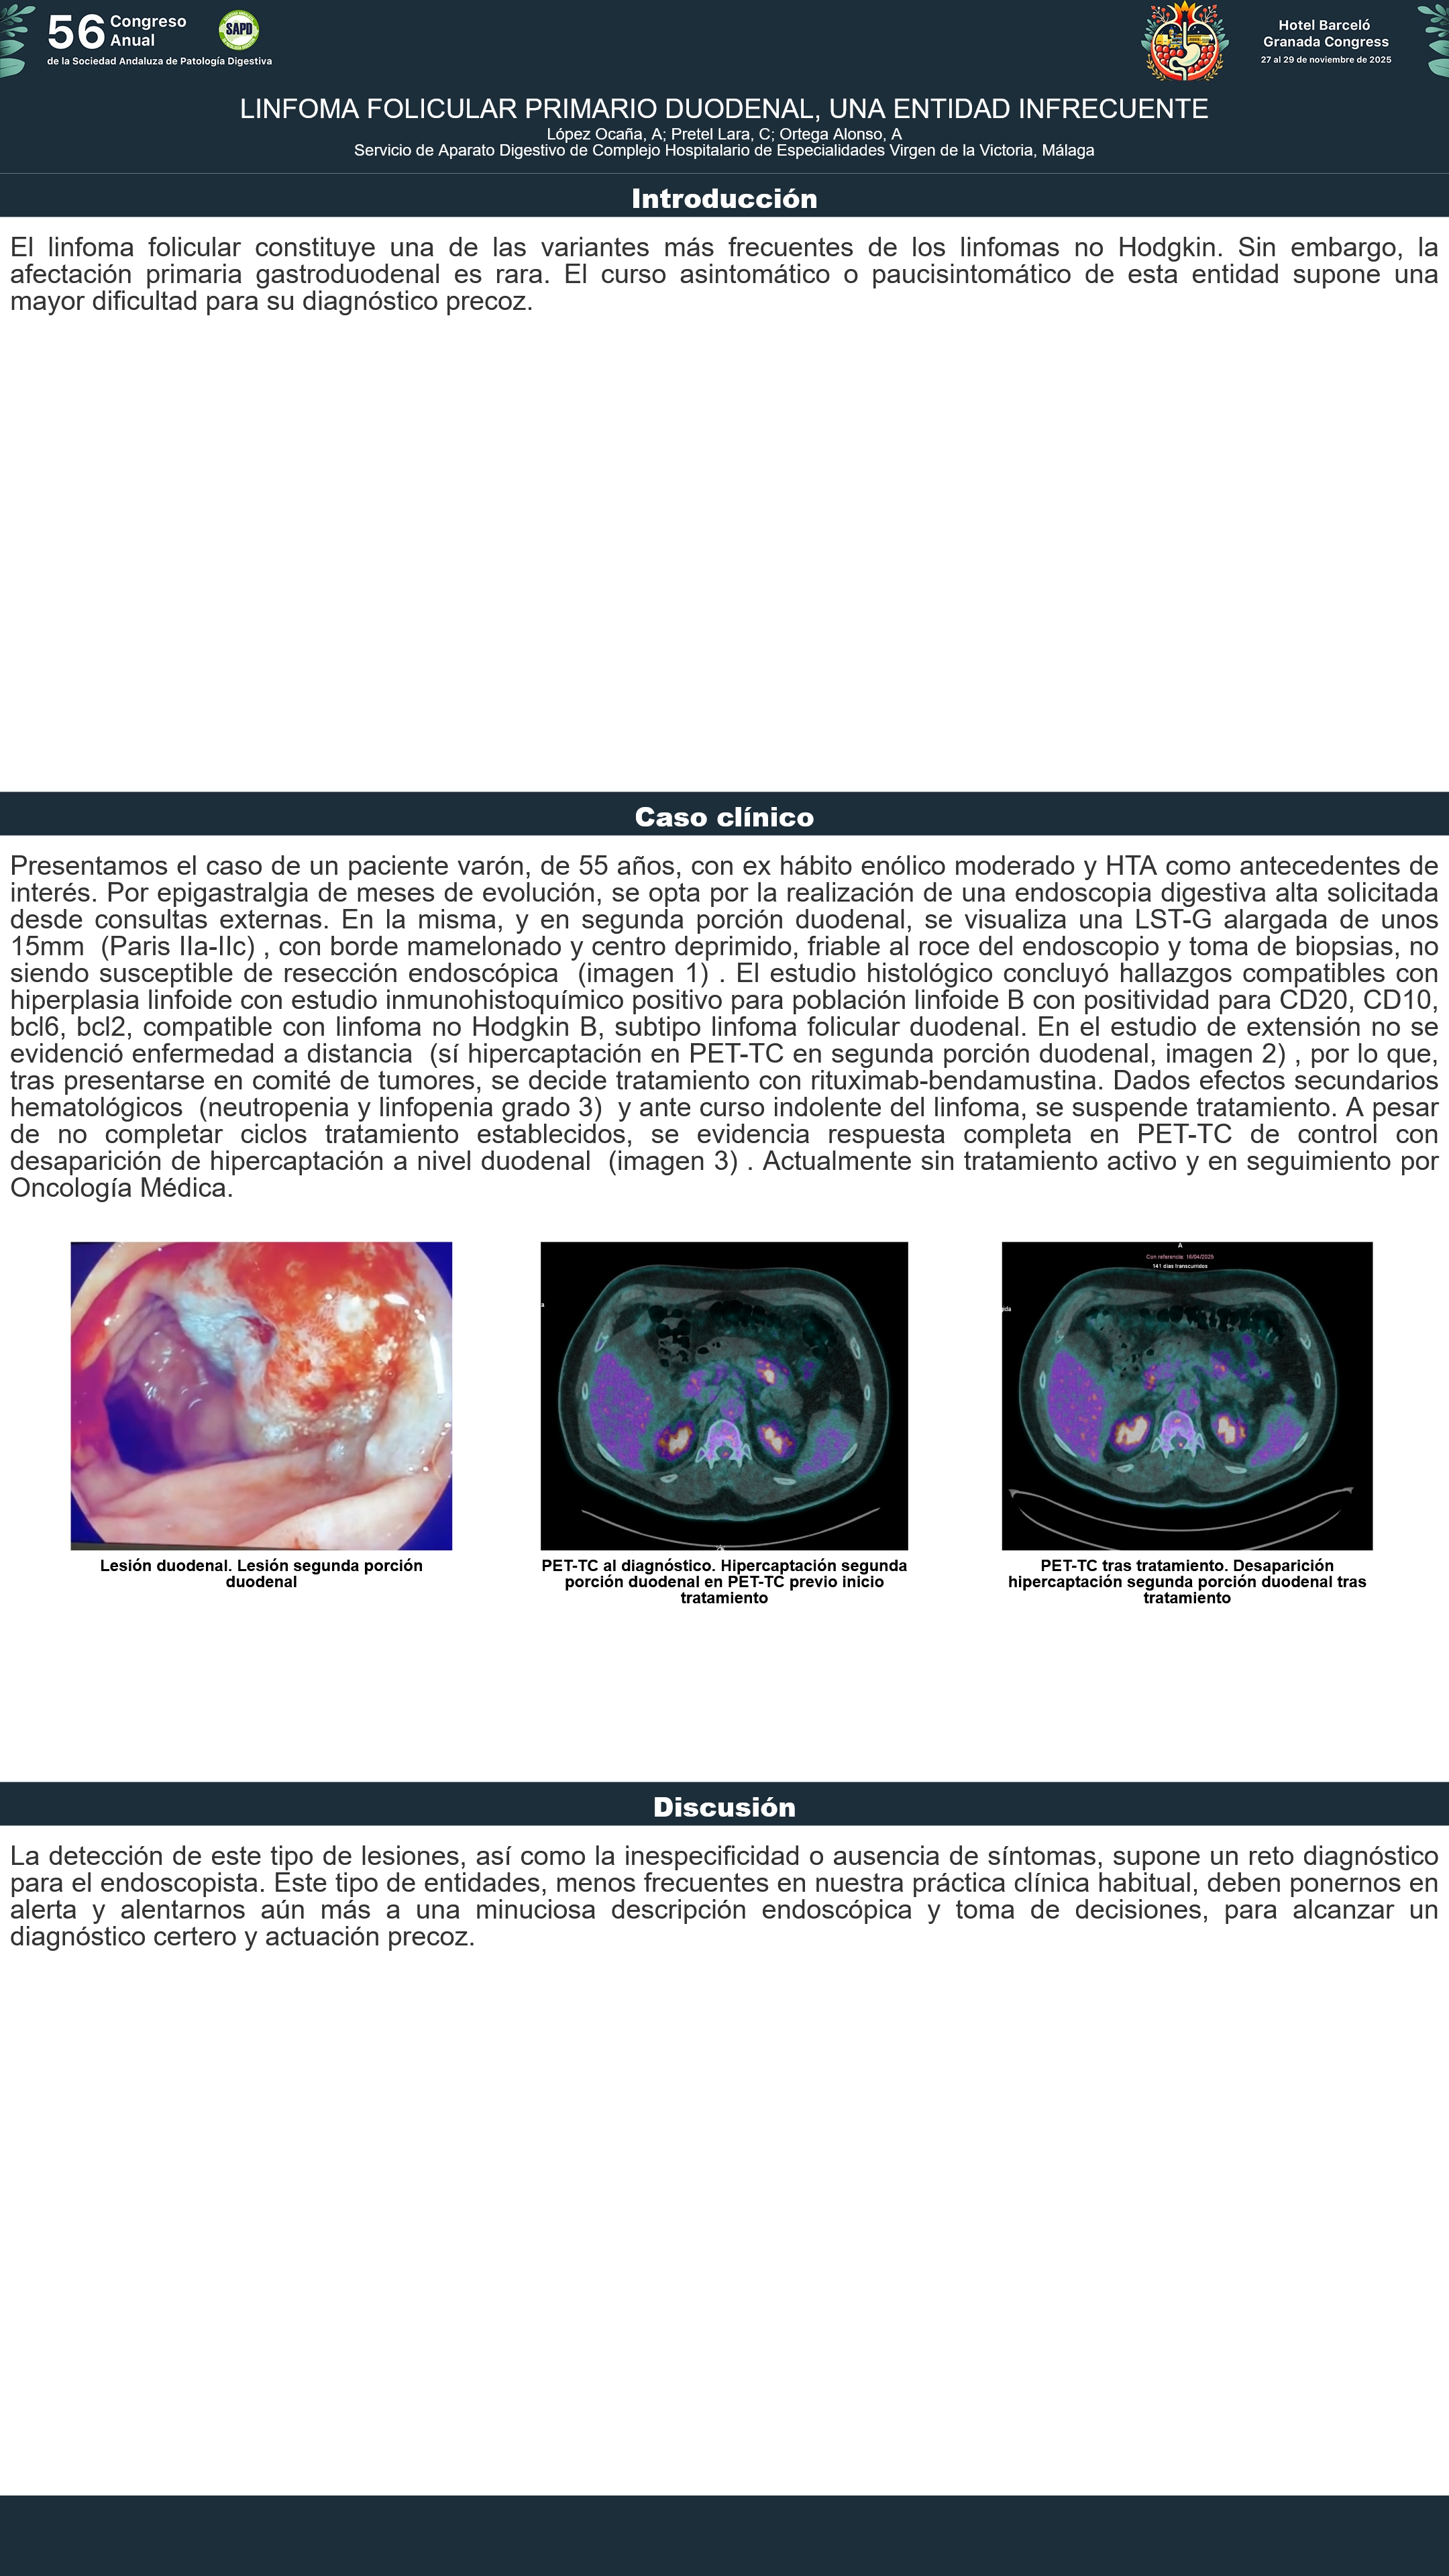

[CP-027] LINFOMA FOLICULAR PRIMARIO DUODENAL, UNA ENTIDAD INFRECUENTE